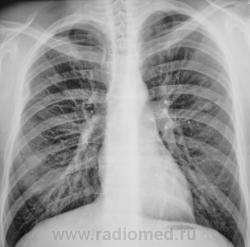

Пол пациента: Мужской пол Тип патологии: Другое Область исследования: Грудная клетка и верхние дыхательные пути Методы исследования: Rg Туберкулома? https://radiomed.ru/sites/default/files/styles/case_slider_image/public/user/12/2.pb240005a.jpg?itok=xfKB85vZ ID:9364 Thu, 25/11/2010 - 01:21 #1 Катенёв Валенти... Offline Last seen: 7 years 3 weeks ago Joined: 22.03.2008 - 22:15 Posts: 54876 Продолжение. [[wysiwyg_imageupload:690:]][[wysiwyg_imageupload:691:]][[wysiwyg_imageupload:692:]][[wysiwyg_imageupload:693:]] Thu, 25/11/2010 - 05:24 #2 Helios Offline Last seen: 7 months 3 weeks ago Joined: 06.08.2010 - 15:16 Posts: 4417 А здесь?Приложения: Thu, 25/11/2010 - 14:34 #3 lupan Offline Last seen: 6 years 10 months ago Joined: 07.01.2010 - 17:17 Posts: 1406 Helios wrote: А здесь? Туберкулома-то имеется. Но не она здесь самая "страшная". Великое преймущество врача заключается в том, что он не обязан следовать собственным советам. ( А. Кристи) Thu, 25/11/2010 - 14:46 #4 Катенёв Валенти... Offline Last seen: 7 years 3 weeks ago Joined: 22.03.2008 - 22:15 Posts: 54876 Наша "туберкулома", конечно, требует д/диагностики с периферическим раком лёгкого. Thu, 25/11/2010 - 21:06 #5 Катенёв Валенти... Offline Last seen: 7 years 3 weeks ago Joined: 22.03.2008 - 22:15 Posts: 54876 Пациент прооперирован в ОПТД, диагноз подтвержден. Снимки ниже.Приложения: Thu, 25/11/2010 - 21:13 #6 Катенёв Валенти... Offline Last seen: 7 years 3 weeks ago Joined: 22.03.2008 - 22:15 Posts: 54876 Фрагменты снимков и томограмма.Приложения:

Туберкулома-то имеется. Но не она здесь самая "страшная".

Наша "туберкулома", конечно, требует д/диагностики с периферическим раком лёгкого.

Пациент прооперирован в ОПТД, диагноз подтвержден. Снимки ниже.